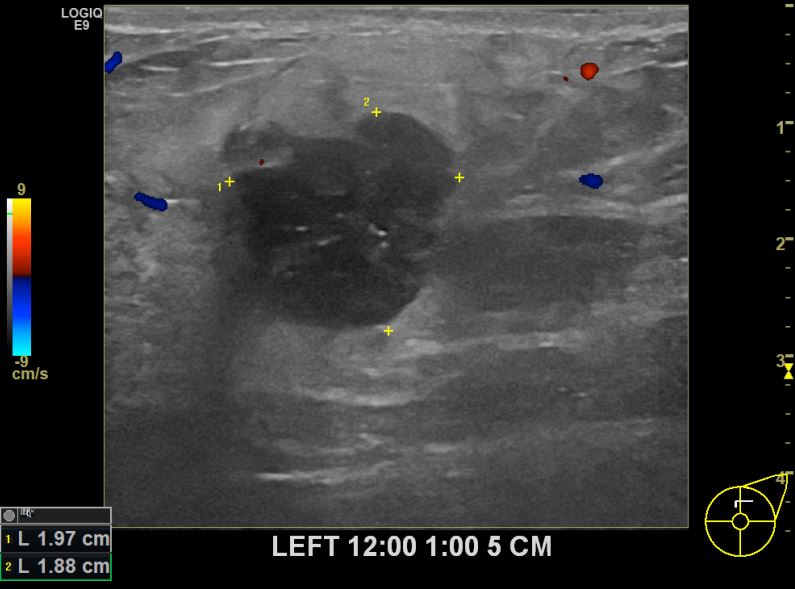

상기환자 건진상 이상소견으로 조직검사권유받고 내원하신 70대 여성분으로 좌측유방멍울  조직검사시행후 유방암 진단되었습니다